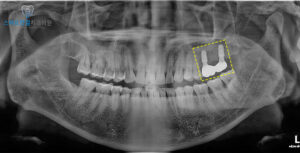

위 환자분께서는

왼쪽 위 치아의 흔들림과

불편함으로 인해

본원에 내원해 주셨어요.

왼쪽 위 큰 어금니 두 개에서

치주염이 발생한 것이

확인되었어요.

먼저 발치를 진행했어요.

이후 임플란트 식립 전,

정밀한 확인을 위해

CT를 촬영했는데요.

촬영 결과,

수직적, 입 천장쪽으로

골 소실이 심각하게 진행된

상태로 확인되었어요.

임플란트만 식립하기에는

뼈의 지지력이 부족해,

추가적인 뼈이식이 필요함을

알 수 있었어요.

화서동치과 스마트한결의

치료 전후 사진이에요.

염증 없이 깨끗하게

임플란트가 마무리 된게 보이시나요?